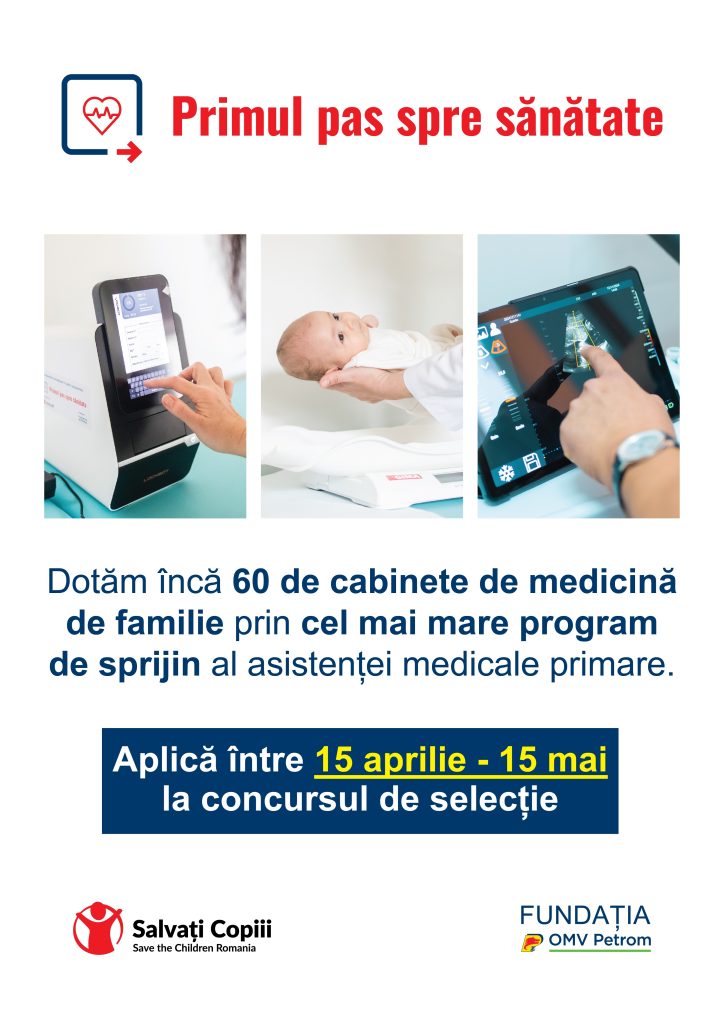

60 de cabinete de medicină de familie din zone dezavantajate vor fi dotate cu aparatură medicală modernă. Cum vor fi selectate cabinetele

Zeci de cabinete de medicină de familie din mediul rural vor fi dotate cu echipamente moderne, printr-un program național al Organizației Salvați Copiii. Inițiativa vine în contextul unor statistici alarmante privind accesul la servicii medicale în zonele defavorizate